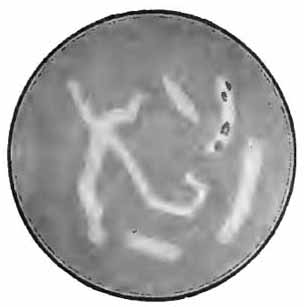

Diplococcus pneumoniæ in the blood

FIG. 9.—Diplococcus pneumoniæ in the blood (Fränkel and Pfeiffer).

Recognition of the pneumococcus depends upon its morphology, the fact that it is Gram-staining, and the presence of a capsule. Numerous methods for staining capsules have been devised, but few are satisfactory. Buerger's method is excellent. It is especially useful with cultures upon serum media, but is applicable also to the sputum. Smith's method usually gives good results, as does also the more simple method of Hiss (p. 263). The sputum should be fresh—not more than three or four hours' old.